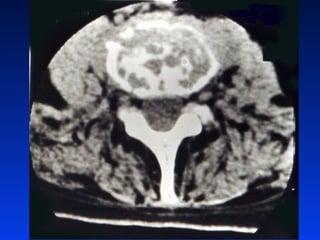

Gaõy luùn nhieàumaûnh CS thaét löng